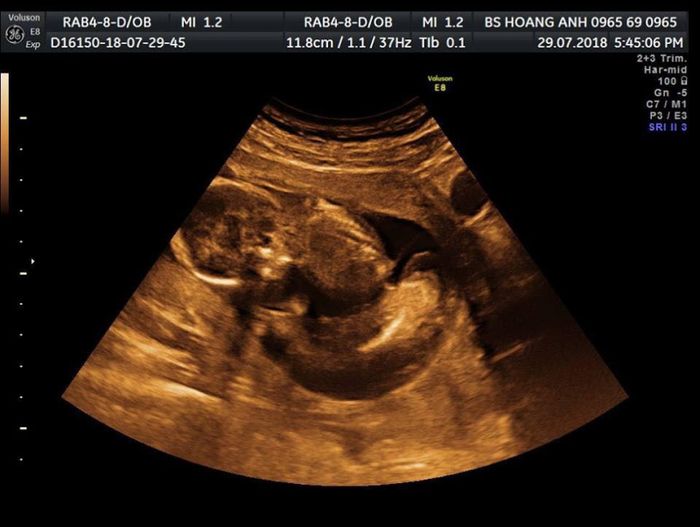

Siêu Âm Thai Chuyên Sâu - Phòng Khám Giáp Hoàng Anh tự hào là địa chỉ uy tín với nhiều năm kinh nghiệm trong lĩnh vực chăm sóc sức khỏe phụ nữ. Tại đây, bạn sẽ được chăm sóc đội ngũ bác sĩ chuyên khoa giàu kinh nghiệm, tận tâm và chu đáo. Với cam kết an toàn và sự tận tụy, phòng khám mang lại sự tin tưởng và hài lòng cho mọi bệnh nhân. Bạn sẽ được chẩn đoán và điều trị chính xác, nhanh chóng trong môi trường hiện đại và tiện nghi.

Lý do chọn Siêu Âm Thai Chuyên Sâu - Phòng Khám Giáp Hoàng Anh:

- Đội ngũ bác sĩ có kinh nghiệm và chuyên môn cao

- Môi trường bệnh viện đạt tiêu chuẩn

- Trang thiết bị hiện đại

- Phương pháp điều trị hàng đầu

- Chăm sóc tận tình từ đội ngũ y bác sĩ

Điện thoại: 0965 690 965